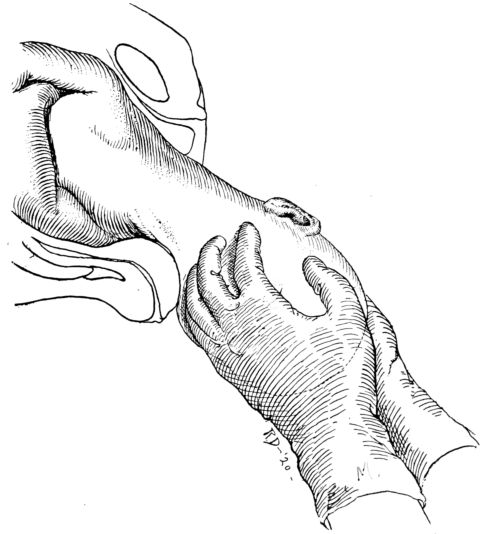

| 69. | Anterior shoulder being slipped from under symphysis | 237 |